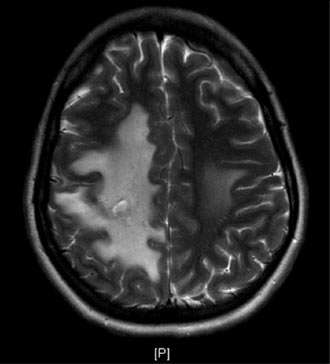

Brain imaging studies such as MRI and CT are commonly used to demonstrate the clot in the cerebral venous sinuses. If necessary, catheter angiography is also performed to visualize the relatively small clots or when catheter based clot-removing treatment is needed (Figure 1).

The blockage can result in brain swelling (edema), stroke, and/or bleeding in the brain (Figure 2).